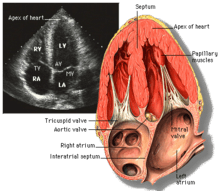

Echocardiogram

Transthoracic echocardiogram uses ultrasonic waves for continuous heart chamber and blood movement visualization. In recent times, it has become one of the most commonly used tools in diagnosis of heart problems, as it allows non-invasive visualization of the heart and the blood flow through the heart, using a technique known as Doppler.

Transoesophageal echocardiogram uses a specialized probe containing an ultrasound transducer at its tip is passed into the patient's esophagus. It is used in diagnosis of various thoracic defects or damage, i.e. heart and lung imaging. It has some advantages and disadvantages over thoracic or intravasular ultrasound.